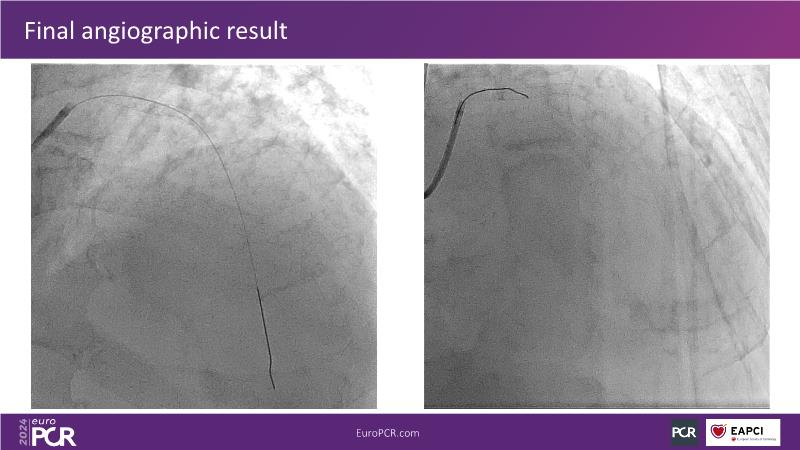

Tune into this 2024 session for insights into the latest ESC guidelines, strategies to prevent and treat no reflow, and an examination of trials like TASTE, TAPAS, and TOTAL on coronary thrombus management. Explore also the outcomes of the CHEETAH study, pondering a potential paradigm shift, and delve into a case study on thrombus removal in a patient with high thrombus burden.